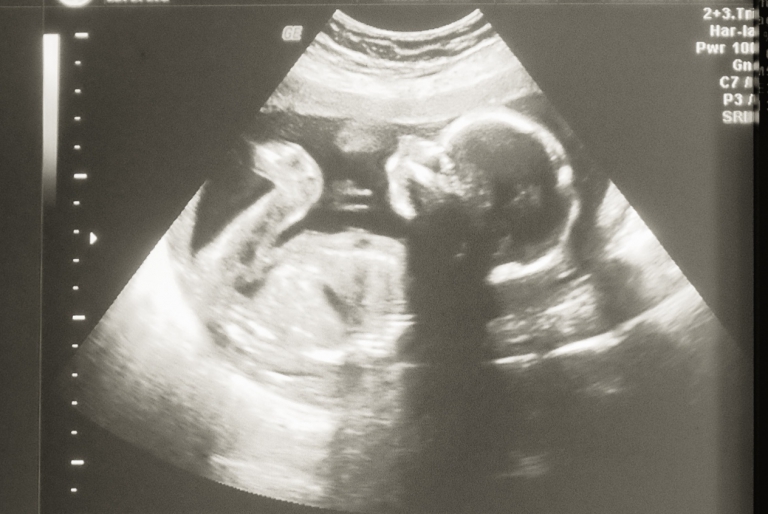

De eerste echo: Ohjee, het zijn er opeens twee!

Eind mei a begin juni 2018 wisten we dat mijn vrouw zwanger zou kunnen zijn en na meerdere malen op een stokje geplast te hebben wisten we het wel zeker: “We krijgen een Baby!” Twee jaar geleden hoopten we ook al zwanger te worden maar wegens gezondheidsproblemen was dit ons toen helaas niet gegund, maar hierover zal ik in een latere blog nog weleens eens keer uitweiden. Wat ons nu overigens opviel aan de ondergeplaste stokjes was dat in een vroeg stadium (paar dagen voor de verwachte menstruatiedag) het streepje al zeer goed zichtbaar was. Mijn vrouw maakte hierover dan ook geregeld grapjes dat het misschien wel een tweeling zou kunnen zijn…

Vlak nadat we deze mooie ontwikkeling ontdekt hadden, gingen we twee weken op vakantie naar de Algarve (in Portugal). De vakantie was heerlijk ontspannen, maar ik was wel eenzaam met mijn alcohol. Mijn buik is op vakantie net zo hard gegroeid als die van mijn vrouw. Na terugkomst in Nederland hadden we 28 juni 2018 een echo ingepland staan en tijdens deze echo werd ons snel onze verrassing medegedeeld: “We waren niet zwanger  van één, maar van twee baby’s.” We hadden een 7-wekenecho en we kregen als officiële uitgerekende datum 11 februari 2019 te horen.  Omdat een tweeling altijd eerder komt, hopen we de 37 weken wél te halen. Alles voor de 37 weken wordt namelijk gezien als prematuur.

Mijn eerste gedachte?! “WTF!!! Wat een kleine kans? Hoe gaan we dit doen? Kan mijn vrouw dit lichamelijk allemaal wel aan? Wat betekent dit financieel?” Het spookte allemaal meteen door je hoofd en dit bleef eigenlijk de gehele dag. Ik kon vervolgens bijnde echo geen woord meer uitbrengen en was totaal van de leg tijdens de autorit van het ziekenhuis naar huis. Pas ’s avonds – na in de middag gewoon weer gewerkt te hebben – kon ik het allemaal een plekje geven en kwam het besef dat wij dit samen kunnen en over hoe mooi dit allemaal zal gaan zijn. Overigens een voorkeur voor een geslacht hebben we niet, voor ons is het belangrijkste dat de baby’s gezond zijn. Gelukkig word je bij een tweelingzwangerschap goed in de gaten gehouden. Zo ben je medisch onder behandeling en zal de bevalling in het ziekenhuis plaatsvinden. De bevalling zal dan ook door de gynaecoloog worden gedaan en niet de verloskundige. Het traject naar de bevalling bestaat uit veel controles en groei echo’s.